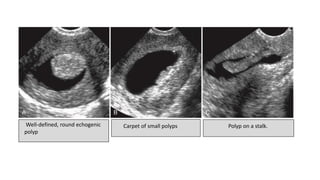

Well-defined, round echogenic

polyp

Carpet of small polyps Polyp on a stalk.